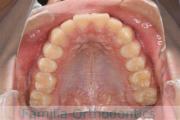

下の前歯が後ろにあるのが気になるとのことで来院されました。非抜歯で行うことも可能でしたが、上下左右から小臼歯抜歯をして治療を行うことをご希望になりました。

マルチブラケット法にて治療を行い、約3年、40回の通院が要でした。

かみ合わせが深い(上の前歯で下の前歯が覆われてしまう)ので、保定をしっかりしないと、また深くなってきてしまいやすいです。

上顎

下顎

前歯の関係など